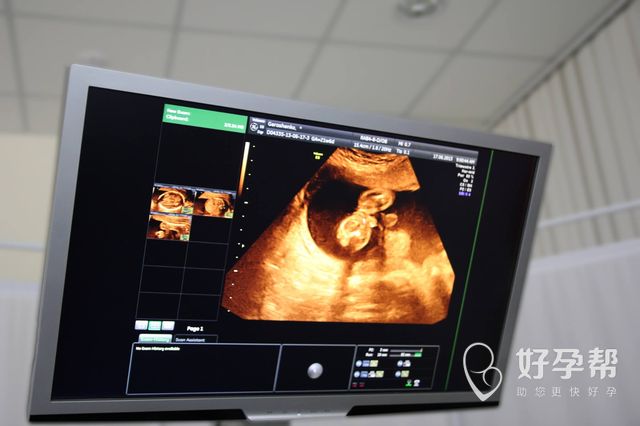

只要去医院看病,那么肯定要选择合适的科室,这样才不会出现问题,但是一般的疾病人们都知道要去哪个科室才能解决问题,而无法生育却会让人产生很多疑惑,如果产生了做试管婴儿手术的想法,那么又要选择什么科室呢?清远人民医院试管婴儿是什么科?这就开始进行这方面的介绍。

清远人民医院试管婴儿是什么科?如果随便寻找一个科室,那么肯定会耽误事情,反而给自己增加了更多的困扰,由于多年前就能够做试管手术了,因此人民医院也有相关的科室,朋友们可以直接前往该医院的生殖科,只要将自己的情况告诉医护人员,很快医院就会做好安排工作,让朋友们能够和专家面谈,或是直接检查了。